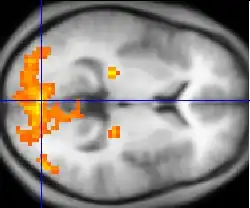

Neuroimaging

Neuroimaging has contributed to the identification of the neural components involved in drug reinstatement as well as drug-taking determinants such as the pharmokinetics, neurochemistry, and dose of the drug. The neuroimaging techniques used in non-human primates include positron emission tomography (PET), which uses radiolabeled ligand tracers to measure neurochemistry in vivo and single-photon emission computed tomography (SPECT).[3] Functional magnetic resonance imaging (fMRI) is widely used in human subjects because it has much higher resolution and eliminates exposure to radiation.[14]